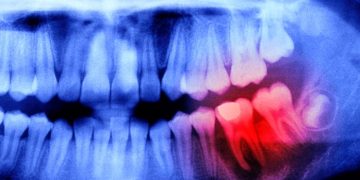

По мнению руководителя группы японских ученых Сатоши Ямагучи, здоровая полость рта благотворно влияет на здоровье мозга. И наоборот, по оценке ВОЗ, тяжелыми формами заболеваний пародонта (ткани, окружающие зубы и удерживающие их в альвеоле) страдают почти 20 % взрослого населения (или 1 млрд. человек), что в конечном итоге может отразиться на раннем снижении их когнитивных способностей.